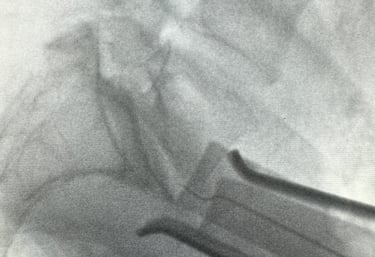

Snapshots of precision in lumbar spine imaging

Precision Imaging

Delivering clear, detailed spinal exposures.